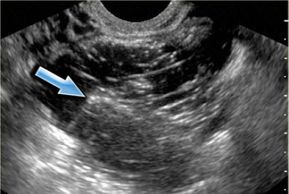

Endometriosis may produce multiple tiny areas of hemorrhage which are difficult to impossible to visualize with ultrasound because of the small size. Larger areas of hemorrhage are termed endometriomas (chocolate cysts), and these may be readily visualized by ultrasound.

Occasionally, the ovary may twist or 'torte' on it's pedicle. This may stop the blood supply to the ovary, producing ischemia and severe pain. The ovary quickly enlarges. It's important to make a correct diagnosis so the ovary can be saved.